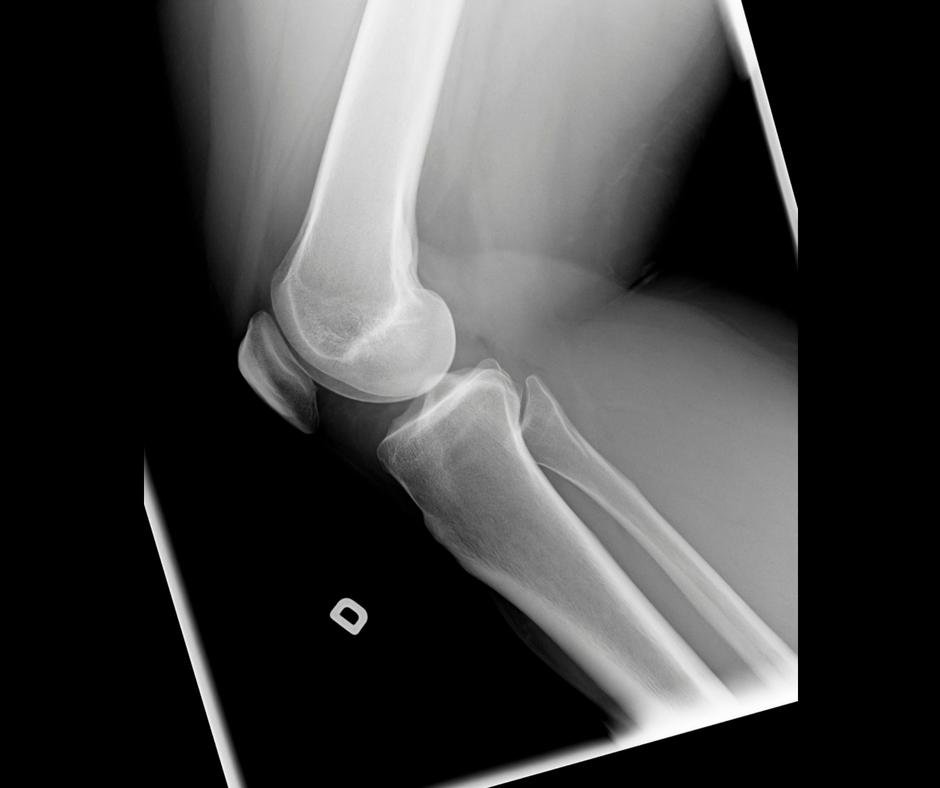

Joint Pain:

Of most concern are the joints of the knee, ankle, elbow, wrist, and shoulder. Joint pain that last more than 48 hours may require a physio evaluation.